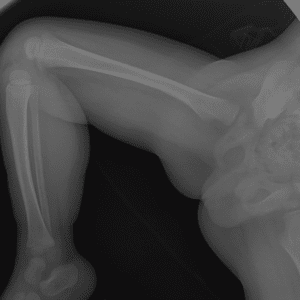

Pediatric Radiographs